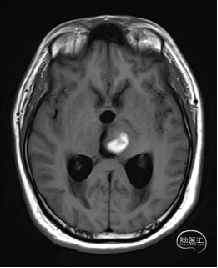

术前MRI检查

术前MRI检查提示左侧丘脑中脑海绵状血管瘤并卒中,梗阻性脑积水;

诊断:1.左侧丘脑中脑海绵状血管瘤并卒中,2.梗阻性脑积水;

年轻患者,较短时间内发生左侧丘脑二次出血,出现右侧面部及上肢麻木,复视,第二次出血后并发梗阻性脑积水,出现头痛。结合病史、神经系统体征、头颅CT及MRI检查,诊断左侧丘脑及中脑CM并卒中、脑积水明确,并导致了神经功能障碍,具备手术指征。

本例患者磁共振检查清晰显示病变位于左侧丘脑中脑区域,且位于丘脑内下方向中脑顶盖延续,病变的上部、前部、外侧部都有重要的神经组织,因此,手术从上方、前方、外侧方向切除病变均难以实施;